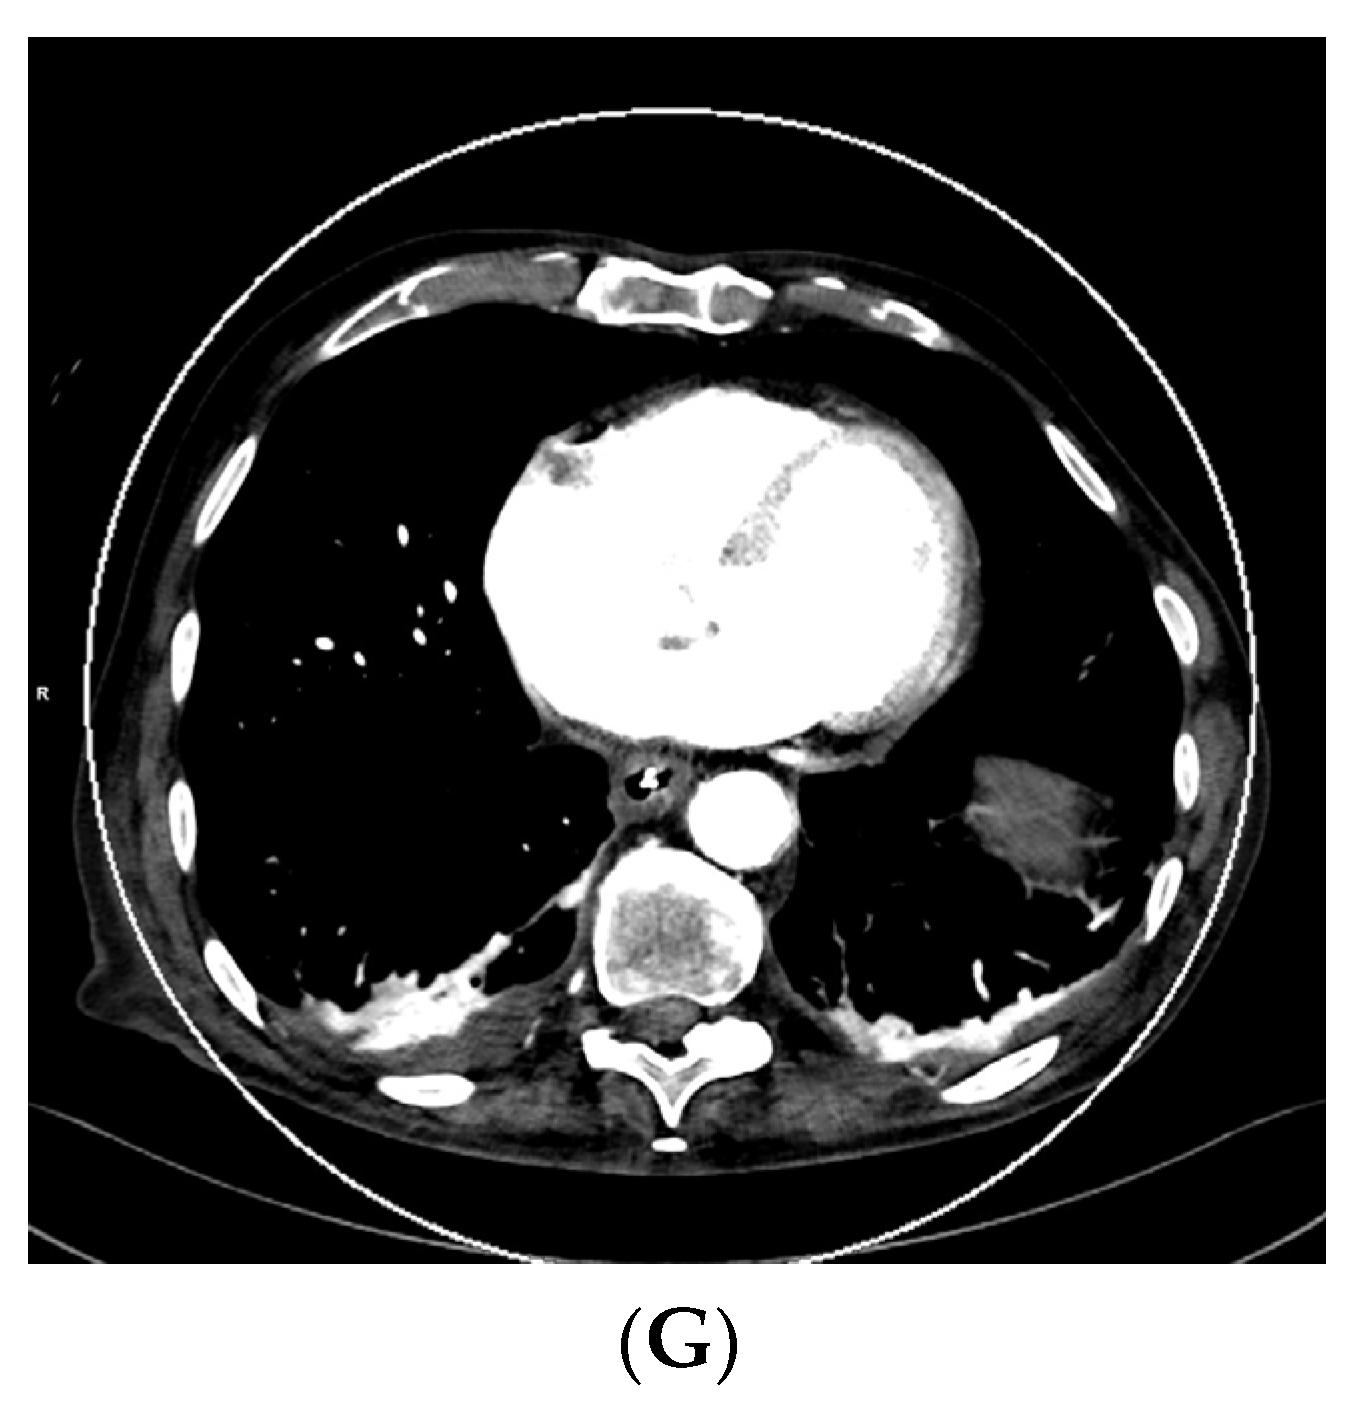

As vascular applications were one of the first fields where the benefits of DECT were demonstrated in studies and applied to routine clinical practice, aortic imaging is one of the essential fields in this context. Using DECT, it is possible to explore the effect of low-kV acquisitions using the K-edge of iodine for improved contrast in series. Martin et al. (2017), Albrecht et al. (2016), and others described that enhanced iodine contrast allows for improved detection of endoleaks; for example, in the context of thoracal or abdominal endovascular aortic repairs thoracic endovascular aortic repair (TEVAR), endovascular aneurysm repair (EVAR), fenestrated endovascular aneurysm repair (FEVAR), as well as insufficiencies and leakage of surgically implemented grafts [17,51,52,53]. Furthermore, this technique can compensate for the missed bolus and insufficient concentrations of iodine to a certain degree. The literature described that the contrast agent amount could be reduced by up to 50% in the vasculature by using 50 kV reconstructions [26]. This could be especially relevant to patients with impaired renal function, which is often associated with generalized vascular disease; however, the low-kV images also have more image noise owing to the higher rate of interaction of the photons with the atoms of the scanned body, which varies in severity depending on the DECT hardware used [6]. Figure 1 shows a case of low intravascular iodine contrast, which was caused by low-output cardiac function, as seen in the VMI reconstruction at 120 kV (Figure 1A).

Figure 1.

Acquisition of a DECT CTA of the thoracic aorta with a bad intravascular contrastation due to low output cardiac insufficiency in a 75-year-old male patient suffering from chest pain, tachycardia, and peripheral edema; (A) shows an axial view 120 kV VMI reconstruction of the descending aorta thoracalis with low intravascular contrast. Further, we see bilateral pleural effusions with adjacent partial atelectasis of the lung parenchyma. Aortic dissection could be ruled out as a cause for the clinical presentation; (B–G) show monoenergetic VMI reconstructions from 40 to 90 kV in 10 kV steps, with increasing contrast from the higher kV reconstruction of 90 kV (B) to the low-kV reconstructions with maximum intravasal contrast in the 40 kV reconstruction (G), which is closest to the K-edge of iodine, which is located at 33 kV. Accordingly, the K-edge peak is found in (G), as the highest intravasal attenuation is found here.

Consequently, VMI reconstruction was used to optimize intravascular contrast by generating monoenergetic reconstructions from 40–90 kV in 10 kV steps (Figure 1B–G, with the maximum contrast visible in the VMI 40 kV reconstruction (Figure 1G). This is especially important in the context of the visibility of small vessels, bleeding, and low-attenuation lesions. Furthermore, iodine mapping can be used to prove the accumulation of extravasal iodine in hematomas and bleeding. Using mixed images, for example, 120 kV, which is calculated from the high- and low-kV images, can improve the image noise. Furthermore, it is possible to create virtual unenhanced images or use other material-specific applications that are derived from (virtual) monoenergetic images. These monoenergetic images can be reconstructed at 40–190 kV for DSCT DECT. In this context, calcium subtraction from calcified plaques is important [17,20].